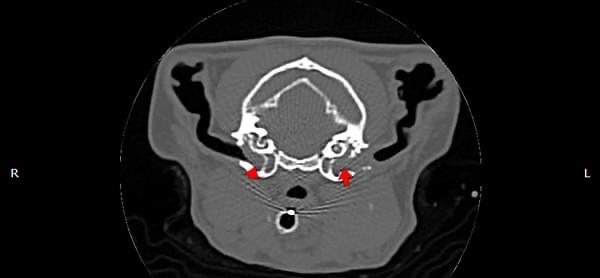

耳道內視鏡探查及電腦斷層發現鼓膜鬆弛部發炎、鼓膜消失,穿刺鼓膜後沖出膿樣物,採樣後確認有細菌感染,確認為中耳炎。

圖為電腦斷層影像